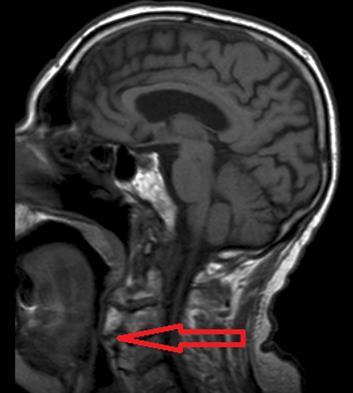

Brain and cervical MRI were performed to exclude recent brain ischemic lesions and to investigate the spinal chord involvement in relation to the known severe osteophytosis. The brain MRI showed only signs of chronic vasculopathy and no images related to acute events. The neck MRI revealed no medullary compression or signal alterations; osteophytes originating from C1 to C7 were described and had a compressive and displacing effect on the upper aero-digestive ways and laryngeal post-cricoid area. Osteophytes were forming bony bridges in the anterior prevertebral space from C3 to C7.

Figure 1.Osteophytes-induced upper airways obstruction

According to the pulmonary consultation and the treatment options, cervical neurosurgery was planned 1 week later and CPAP was not started because the consultant hypothesized a possible negative traumatic effect of positive pressure airflow on a so rigid obstacle through an edema-mediated mechanism. No symptomatic episodes happened during the hospitalization and the patient was discharged. At home, the patient suddenly died before surgery, during the night.